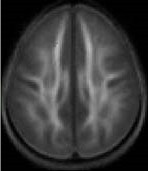

Following the instruction, there were no differences between the poor and average readers with respect to the quality of their white matter. Source: Timothy Keller, Ph.D.; Marcel Just, Ph.D.